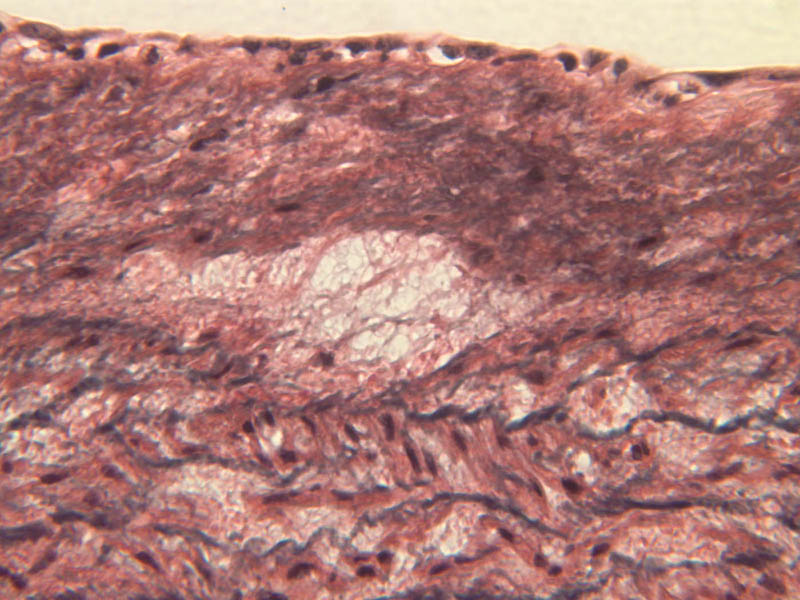

Blood passes from the elastic arteries via arteries of intermediate type into the muscular (distribution) arteries. Locate and examine a muscular artery in slide A-28 (Renal artery & vein, H&E [2.5x, 10x-labeled, 20x, 40x-labeled] [10x-labeled, 20x, 40x]; AF [10x-labeled, 20x, 40x]). Note that the tunica intima is separated from the tunica media by a thick internal elastic membrane which has a scalloped appearance. The tunica media consists of many layers of smooth muscle cells arranged concentrically in a spiral fashion (A-28, H&E [2.5x, 10x-labeled, 20x, 40x] [2.5x, 10x, 20x, 40x, 40x] [2.5x, 10x, 20x]). An external elastic membrane is present, but is thinner and less complete than the internal elastic membrane. The tunica adventitia is about equal in size to the media in this vessel and is more intensely eosinophilic in its staining properties. Note the appearance of small blood vessels in the outer part of the tunica adventitia. You may also be able to see occasional nerve fibers.